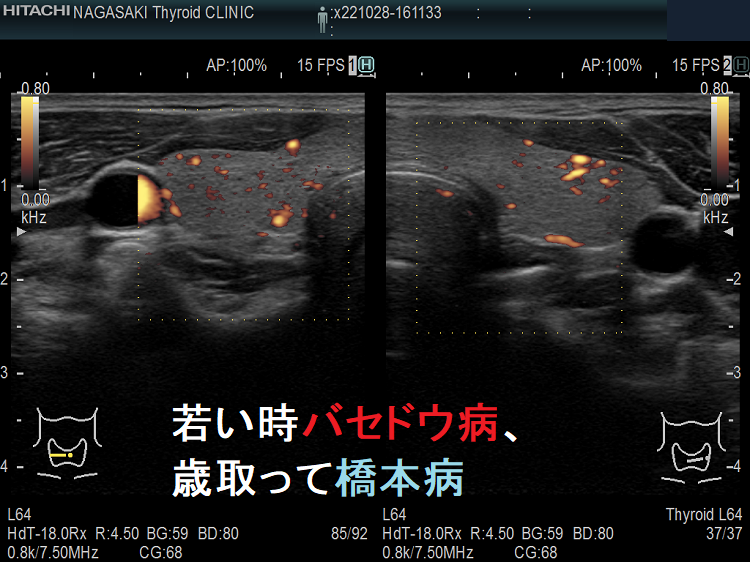

よくあるパターンは「若い時、バセドウ。齢(とし)いって橋本」と言うやつです。(当然、逆もあり)